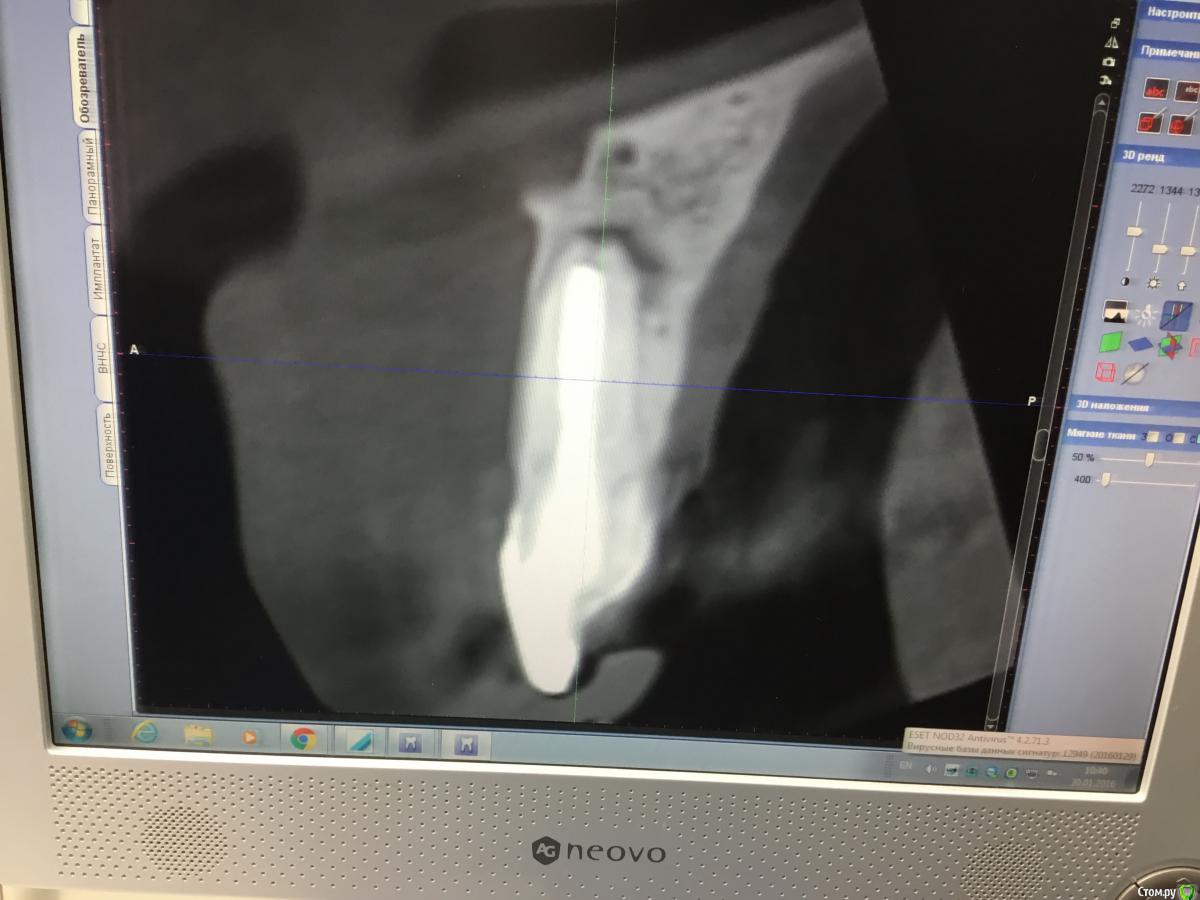

Zorrro Опубликовано 6 марта, 2016 Поделиться Опубликовано 6 марта, 2016 (изменено) Мой постоянный пациент привёл своего сынишку с жалобами на свищь на нёбе.Сделали кт и решили ,что вначале переберём каналы,а через пол года будем посмотреть куда нам двигаться дальше… Эстетика коронки на 11 вполне устраивала пациента,тем более он был уверен,что поставилимплант и вследствии коронку популярный доктор используя новейшие технологии и материалы,позволяющие не прибегать к устаревшим костным и ещё каким-то пластикам.запись к доктору уходила на пол года вперёд и молодой человек чудом втиснулся в этот плотный график,чтобы отхватить немножко и себе этих самых "новейших" технологий под нос. Фото ещё раз показывает,чтосамое главное в успехе частной практики это ВЕРА доктора в себя и то,что он делает.меня же коронка устраивала тем более,потому что переделывать её вместе с имплантом мне крайне не хотелось.обошлись комментарием про усиленную гигиену и регулярные наблюдения раз в пол года. итак занялись посильным трудом:отмыли 21 и 22,констрикция убежала за 50.02,остановились на 70.02 стальными файлами отступя 1мм,метапекс,через 2 недели irm и стекловолокно нафуджи+,филтек.договорились про контроль через пол года и коронки если всё ок. Ещё немного срезов до и преимущество кт перед прицельными снимкамиИ сразу после. Про коронки и корневой герметизм пациент не понял и решил оставить бломбы на месте. Изменено 6 марта, 2016 пользователем Zorrro 1 Ссылка на комментарий